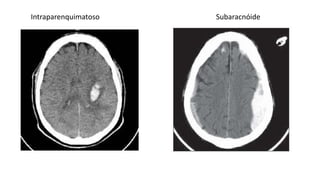

Intraparenquimatoso Subaracnóide

AVC Hemorrágico

• Ocorre quando há rompimento de um vaso ou artéria cerebral

• O mais comum é o intraparenquimatoso

• Acomete menor número de pessoas porém é mais frequentemente

fatal

• A principal causa do AVCH intraparenquimatoso é a HAS crônica já a

do AVCH subaracnóideo é ruptura de aneurismas

• Pode ocorrer também por vasculite, distúrbio de coagulação do

sangue, insuficiência cardíaca, entre outros